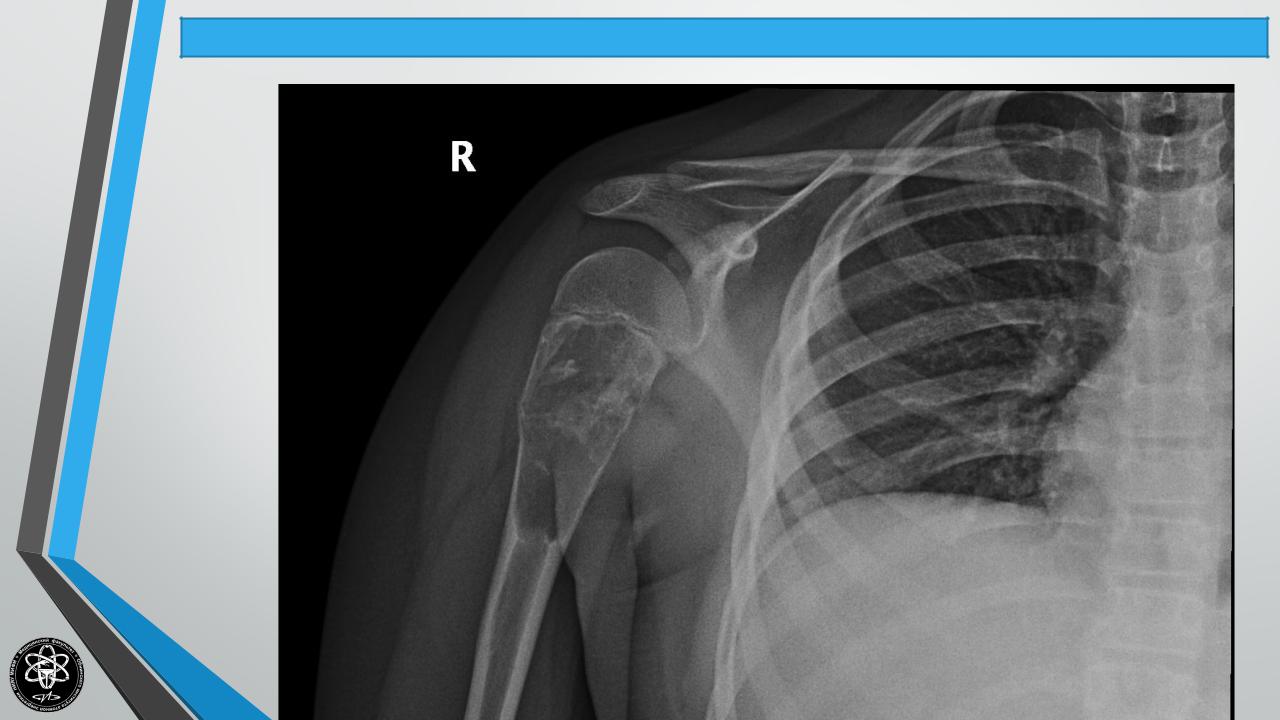

ОСТЕОБЛАСТОКЛАСТОМА(КОСТНАЯКИСТА, Частные вопросы костной онкологии

ГИГАНТОКЛЕТОЧНАЯОПУХОЛЬ, АНЕВРИЗМАКОСТИ)

Частота — 7,6% опухолей скелета. Поражаемый возраст — 10 — 40 лет.

Частота у мужчин и женщин примерно одинаковая. Формы: литическая и ячеистая.

Течение прогрессирующее. Возможны метастазы, малигнизация, особенно в старших возрастных группах. Рост экспансивный. Кость постепенно утолщается, деформируется.

Излюбленная локализация — метафизы плечевой кости, большеберцовой кости, бедра (нижний метафиз), позвонки и др. Клиника — незначительные боли или полное их отсутствие. Чаще диагностика случайная в связи с патологическим переломом. Рентгенологически — раздутая кость с просветлением в центре ячеистого или литического характера.

Гистологически — полость, заполненная бурой жидкостью. Стенка выстлана грануляционной тканью бурого цвета (“бурая опухоль”).

Лечение — хирургическое — краевая или сегментарная резекция. При недостаточной радикальности — рецидивы, возможны метастазы, малигнизация.